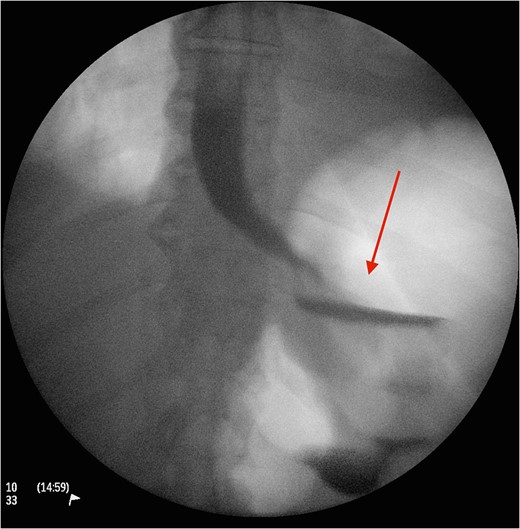

CT image demonstrating the air loculation site next to the band (red arrow).

The gold standard investigative modality is endoscopy [5]. CT is another option, although such tool is more useful in detection of associated complications such as extend, site and type of perforation and/or contaminations. Upon detection of erosion, removal remains the only option and should be performed promptly to avoid associated mortality and morbidity. The use of prophylactic antibiotics in such circumstance is not clear but in our centre we highly recommend their use upon suspicion of diagnosis. In case of band migration and/or erosion, endoscopic removal has shown promising results, although such technique is not always applicable and their open retrieval has been suggested and performed. Another option is standard laparoscopic division and retrieval. Although feasible and successful, this method does not always permit a comprehensive visualization, dissection and division. In our reported case, we encountered the aforementioned factors. Therefore, the decision was made to create anterior gastrotomies (extension of the port to stomach) to facilitate full division, retrieval of the gastric band and assessment of the erosion and its repair if necessary through transgastric approach. The authors believe, such procedure is safe and feasible in circumstances when standard laparoscopic retrieval is not possible. Placement of a new gastric band is usually delayed for a period of 3 months in such cases [3, 5]. In the reported case, patient made an uneventful recovery and was discharged 3 days following the procedure.